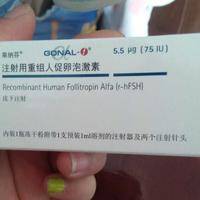

试管促排期间打的针都是用一样的药吗?

问题描述:我马上就要去做试管促排治疗了,听人说要打很多次针剂,说是为了促进卵泡更好的发育。我最近去医院检查的时候,碰到差不多一个时间治疗的姐妹,后面了解到我们的药都一样,所以我想问问这期间都是用一样的药吗?最佳回答:不一定,促排治疗会根据每个患者的具体身体情况来给出合适的治疗建议,因此促排用药会不一样。试管女性在促排之前,医生都会根据方案和具体身体状况来给出用药建议,在这种情况下自然促排针的药就不...

多囊做试管促排药用果纳芬还是丽申宝效果更好?

问题描述:因为我是多囊,所以和老公商量之后就去做试管婴儿,前期的检查还不错,医生让我明天就开始促排了,而我姐妹听说我要促排了,就建议我使用果纳芬,说这个效果好,但是我看网上有人说丽申宝好,各有各的说辞,都给我搞混乱了,所以想问问在促排期用果纳芬好还是丽申宝的效果更好呢?最佳回答:这两种药物的促排卵效果几乎相同,都能有效促进卵泡的发育。丽申宝和果纳芬的主要区别在于药物的纯度、价格和副作用。果纳芬是一...

试管打促排针第8天打欧加利对卵泡能起到什么作用?

问题描述:我最近在陪老婆做试管治疗,在治疗前7天都是打的普丽康这种促排针,但在第8天的时候医生突然给加了个欧加利,而且这药还不便宜。我在网上搜了下还是不太了解对卵泡能够起到的作用,所以想问问大家了解不?最佳回答:打促排针期间打欧加利能够使得卵泡发育更好,使得最终取卵结果较好。这个药其实就是醋酸加尼瑞克,其是一种合成的与内源性促性腺素释放素,在使用后能够帮助女性更好的进行促排卵,从而获得更多优势卵泡...